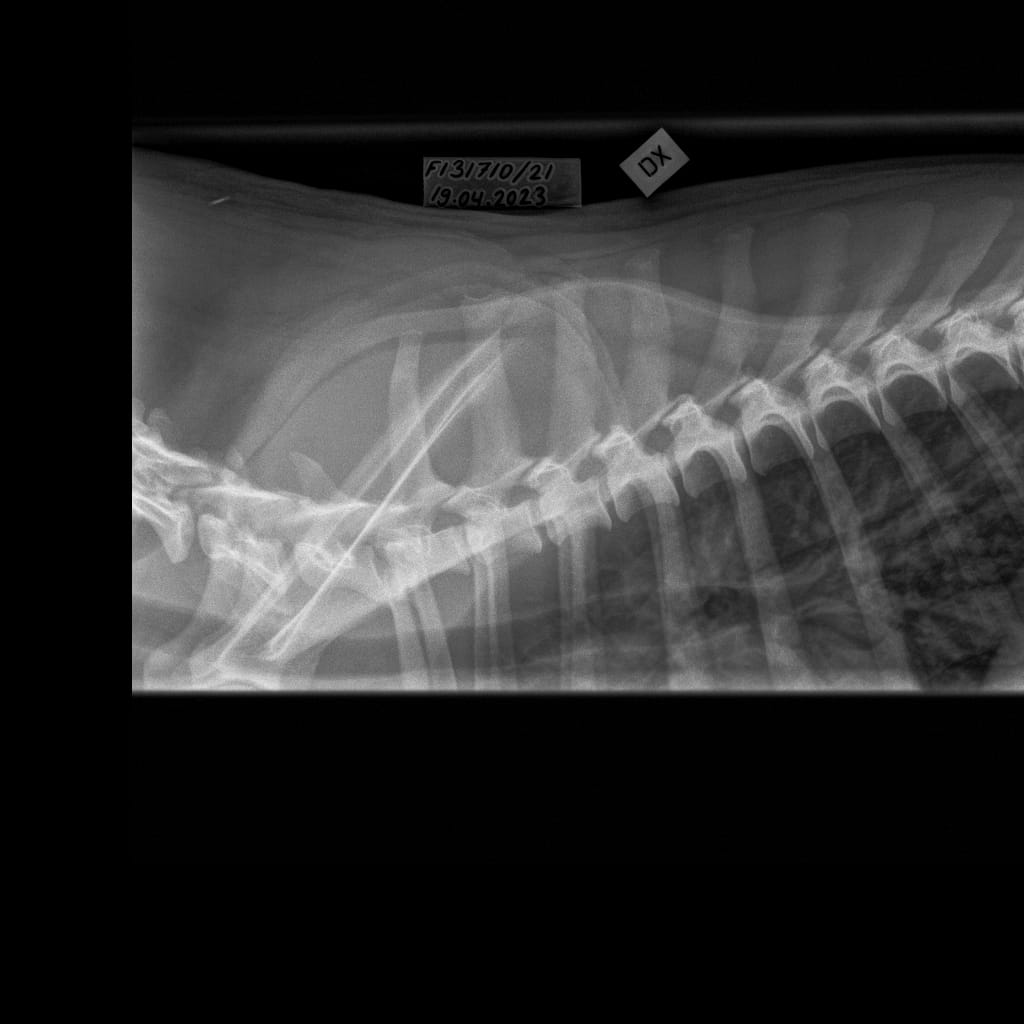

| Name | ID | Birth weigth | Ridge | Height | Weight | Bite | Hips | Elbows | Shoulders | Spine | MH | Other |

|---|---|---|---|---|---|---|---|---|---|---|---|---|

| Lumottu Uljas Iivonpoika ft. Finnridge | Blue ♂︎ | 505 g | Correct | TBA | TBA | TBA | B/B | 0/0 | Unaffected/Unaffected | LTV1, SP0, VA1 | MH, gunshot proof | Low-grade MCT removed 06/2024 |

| Lumottu Aatos Iivonpoika ft. Finnridge | Turqoise ♂︎ | 530 g | Correct | TBA | TBA | TBA | B/B | 0/0 | Unaffected/Unaffected | LTV2, SP0, VA0 | MH, gunshot proof | |

| Lumottu Martta Iivontytär ft. Finnridge | Lime ♀︎ | 525 g | Correct | TBA | TBA | TBA | A/A | Xray: 0/0 CT: 3/1 | Unaffected/Open to interpretation | LTV0, SP0, VA0 | MH, unfamiliar to gunshot | |

| Lumottu Armas Iivonpoika ft. Finnridge | Orange ♂︎ | 440 g | Correct | TBA | TBA | TBA | A/A | 0/0 | Unaffected/Unaffected | LTV0, SP0, VA0 | MH, unfamiliar to gunshot | |

| Lumottu Aulis Iivonpoika ft. Finnridge | Aqua ♂︎ | 440 g | Correct | TBA | TBA | TBA | B/B | 1/1 | Unaffected/Unaffected | LTV1, SP0, VA0 | Handler interrupted | |

| Lumottu Irma Iivontytär ft. Finnridge | Pink ♀︎ | 550 g | Correct | TBA | TBA | TBA | C/B (low sockets) | 0/0 | Unaffected/Unaffected | LTV0, SP0, VA0 | Spring 2024 | |

| Lumottu Sirkka Iivontytär ft. Finnridge | No collar ♀︎ | 390 g | Ridgeless | TBA | TBA | TBA | A/A | 0/0 | Unaffected/Unaffected | LTV1, SP0, VA0 |